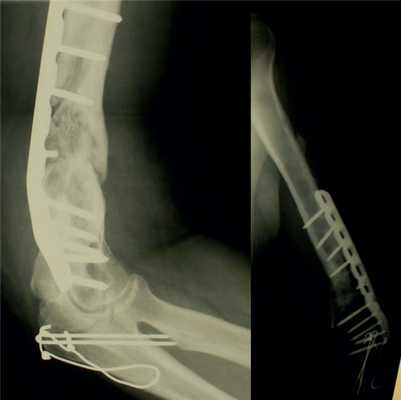

У остальных пациентов 1-й группы внутренние фиксаторы и фиброзные ткани между фрагментами удаляли во время операции, производили адаптацию костных фрагментов с восстановлением оси сегмента и выполняли накостный остеосинтез (или реостеосинтез).

Основная концепция реконструктивной операции - хорошая биологическая совместимость имплантата и хирургическая техника, обеспечивающая бережное отношение к мягким тканям и костным фрагментам. Для остеосинтеза (или реостеосинтеза) использовали оригинальные накостные пластины: динамические компрессирующие (DCP), динамические компрессирующие ограниченного контакта (LC-DCP) и пластины с угловой стабильностью (LCP).

У 17 пациентов наблюдали гипертрофический ложный сустав плечевой кости. В таких ситуациях оперативное лечение имело целью восстановление механической конструкции (жесткости) сегмента.

В ходе операции вскрывали костномозговые каналы, концы фрагментов освежали и фиксировали в анатомически правильном положении без полного удаления фиброзно-хрящевой ткани.

У 14 пациентов отмечали гипотрофический (или атрофический) ложный сустав. Для оптимизации условий процесса сращения таким пациентам выполняли декортикацию или аутотрансплантацию костной ткани в дополнение к стабильной внутренней фиксации.

У 6 пациентов с атрофическими ложными суставами, ранее неоднократно оперированных, наряду со стабильной внутренней фиксацией для поддержки остеогенеза применяли свободные реваскуляризируемые или ротированные на сосудистой ножке надкостнично-кортикальные аутотрансплантаты.

2. Больная В., 47 лет, поступила через 2 года после автотравмы с диагнозом: атрофический ложный сустав правой плечевой кости, перелом фиксатора (рис. 2). Рисунок 2. Рентгенограммы больной В., 47 лет (I), и функция конечности через 2 нед после операции (II). I: а - многооскольчатый перелом правой плечевой кости, б - интрамедуллярный остеосинтез, в - несостоятельность фиксатора через 3 мес, г - реостеосинтез пластиной с угловой стабильностью, д - перелом накостного фиксатора спустя 18 мес, е - реконструкция плечевой кости - накостный остеосинтез метафизарной пластиной с применением ротированного на сосудистой ножке надкостнично-кортикального аутотрансплантата, ж - консолидация ложного сустава через 5 мес; II - функция конечности через 2 нед после операции.

У 2 пациентов 3-й группы с хроническим остеомиелитом в стадии ремиссии выявлен ложный сустав плечевой кости. Им выполнена реконструктивная операция с применением ротированных надкостнично-кортикальных аутотрансплантатов для поддержки остеогенеза в условиях наружного чрескостного остеосинтеза по Илизарову.

В 5 наблюдениях при инфицированных ложных суставах и несросшихся переломах выполнены удаление металлоконструкций, некрэктомия концов костных фрагментов и наружный чрескостный остеосинтез по Илизарову. 3 пациентам операция дополнена пластикой костной раны фрагментами трехглавой (2) и плечелучевой (1) мышц.